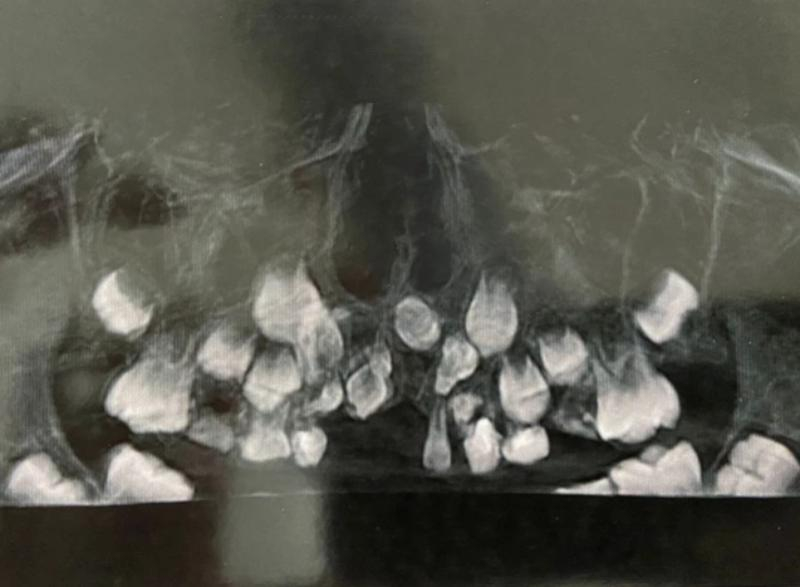

В ходе осмотра врачи обнаружили, что в верхней челюсти мальчика расположены сверхкомплектные зубы необычной формы, расположенные хаотично. Они мешали обычным зубам развиваться, а ребенку нормально жить. Это, по словам медиков, крайне редкий случай, с которым они сталкивались редко. Вызван он вероятнее всего аномалией развития.

— Технически эту операцию не назвать сложной, хотя длилась она порядка полутора часов. Но фактически процедура весьма непростая. Сверхкомплектные зубы скрыты в кости. Их видно на снимке, но манипуляция в кости несет в себе определённые риски, — сообщил челюстно-лицевой хирург ОДКБ Сергей Карнута.

На фото: редкая аномалия видна на снимке фото: Минздрав РО